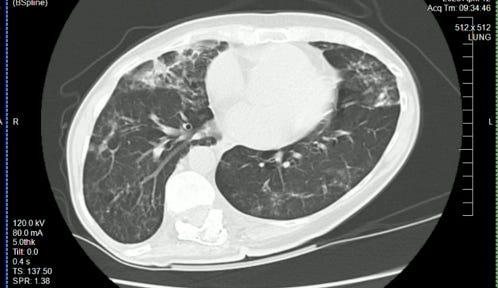

My mom had a chest CT scan prior to starting her alternative treatment. I mailed a disc of the files to Pierre as he’d graciously offered to review them. On March 13, he texted me:

looks like classic MAI given heavy involvement of right middle lobe and left middle lobe (lingula), but also had more diffuse involvement in lower lobes supporting why she was so symptomatic - generally, with only RML and lingula involvement, patients dont have symptoms.. hers became a more diffuse infection

On April 12, my mom had a follow-up CT scan. The report reads in part:

IMPRESSION: Unchanged multifocal interstitial and groundglass opacities as well as scattered tree-in-bud nodules and calcified granulomata. Findings are compatible with sequela of prior granulomatous disease versus atypical mycobacterial infection. No evidence of progressive pulmonary fibrosis or other suspicious short interval change.…

LUNGS/PLEURA: Again seen are multifocal interstitial and groundglass opacities as well as scattered tree-in-bud nodules with a lower lung predominant distribution. Mild emphysematous changes also present. Scattered subcentimeter pulmonary nodules are not suspiciously changed from prior, many of which are calcified compatible with benign granulomata. No evidence of progressive honeycombing or bronchiectasis. Segmental atelectasis in the right middle lobe is unchanged. No pleural effusion.

Imaging (CT chest):

Tree-in-bud nodularity

Middle lobe and lingular predominance

Multifocal interstitial/ground-glass changes

Stable over serial imaging